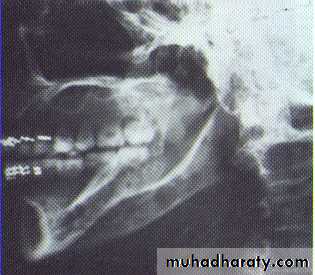

Large multilocular aneurysmal bone cyst

in the ramus with marked expansion andthe displacement of/8.

It is non-neoplastic ,exaggerated , localized, proliferative lesion of vascular tissue, containing giant cells.

It’s a variation of the central giant cell granuloma , can be diagnosed only by histological examination